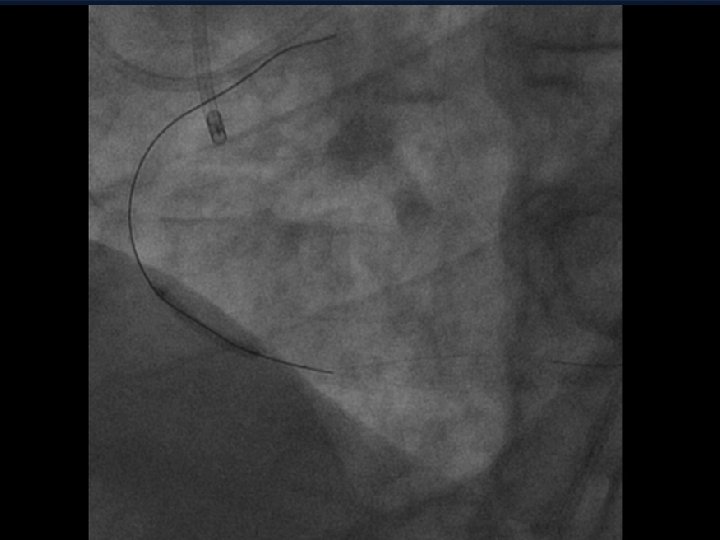

When Do You Need to Snare or Externalize a Wire ? • In a Retrograde Crossing Case when the Wire and/or Support Device Reach the Ostium of the Occluded Artery, you can: 1. Directly Dilate Retrograde, then cross ante. 2. Steer the wire into the guide and use a trapping balloon to improve support 3. Position the support device in the guide and externalize a long wire 4. Snare the wire and Externalize

When Do You Need to Snare or Externalize a Wire ? • In a Retrograde Crossing Case when the Wire and/or Support Device Reach the Ostium of the Occluded Artery, you can: 1. Directly Dilate Retrograde, then change 2. Steer the wire into the guide and use a trapping balloon to improve support 3. Position the support device in the guide and externalize a long wire 4. Snare the wire and Externalize